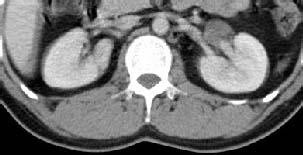

1.患者因体检发现左肾囊肿近1年收住入院。 2.患者于近1年前在体检中发现左肾囊肿,随后到中山大学第二附属医院行CT检查,提示“左肾盂旁囊肿(直径约51.5mm)”,一直未予进一步治疗,近1年来时有轻腰背酸痛不适,无畏寒发热,无肉眼血尿,约2月前在当地医院复查CT,提示肾囊肿大小约76*35mm,现觉病重,要求手术治疗来诊,门诊拟“肾囊肿”收入我科。

专科情况:双肾区无隆起,无压痛及叩击痛,双输尿管行程无压痛及反跳痛,膀胱区无隆起, 叩诊空虚,无压痛。双侧阴囊皮肤无红肿。外生殖器正常。直肠指检:前列腺不大,中央沟存在,质韧,无压痛,肛门括约肌张力正常。 辅助检查:2015-6-30当地8医院上腹部增强CT:左肾囊肿;肝多发囊肿。

病理:(左肾)送检直径1.5cm碎组织一堆,囊壁样。镜下:送检囊壁样组织,囊壁披覆单层上皮,囊壁内肾小管萎缩,肾小球玻璃样变,病变符合肾囊肿。 肾盂旁囊肿又名为肾盂周围囊肿;起源于肾窦外、侵入肾窦的囊肿命名为肾盂旁囊肿。肾盂旁囊肿多由先天性因素造成。 肾盂旁囊肿因是良性病变,囊肿小且无症状,可定期随访,当囊肿直径>5cm,或出现压迫症状及并发症时,应积极采取手术治疗。手术方法有开放性囊肿去顶减压术,B超引导下穿刺抽吸囊内液注射硬化剂以及腹腔镜囊肿切除术等。 随着腹腔镜技术的不断普及和发展,腹腔镜囊肿去顶术必将成为肾盂旁囊肿治疗的首选方法。